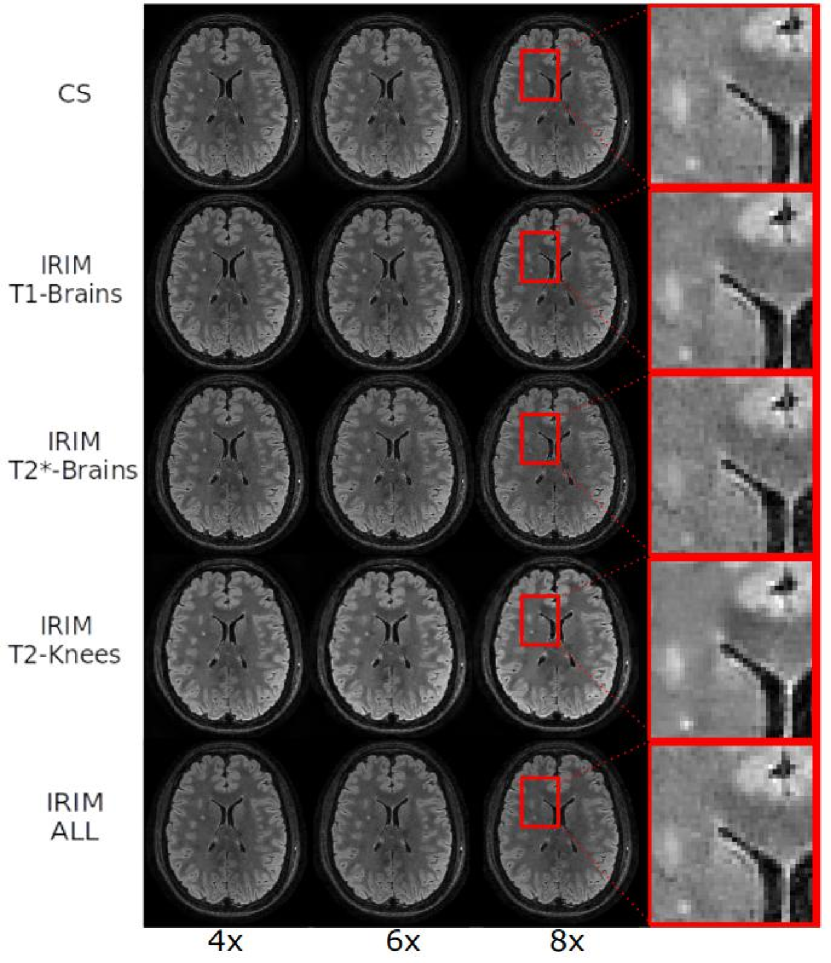

Fig. 6 depicts the results of the lesion simulation experiment. The graphs in Fig. 6(a) show the reconstructed intensity in the centre of the lesion as a function of the simulated intensity. Furthermore, different acceleration factors were applied, whereas applying the IRIM trained on the different modalities individually and all of them simultaneously, as well as the conventional CS reconstruction algorithm. Observe that the intensities are expressed through the multiplication factor of the Gaussian profile added to the original signal. Also, noise was added to the data, so that reference intensity fluctuates somewhat, as indicated by the black line. For 4-fold acceleration, all models had comparable performance, i.e. within a margin of 5%, and showed no bias. For higher accelerations the IRIM trained on the -weighted knee dataset resulted in the highest intensities, even overestimating the reconstructed lesion intensity by 10%, whereas CS underestimated it by 40%. IRIMs trained on the -weighted brain dataset and all datasets underestimated the intensity by 15% and the IRIM trained on the -weighted brain dataset by 45%. This also can be observed in the reconstructions in Fig. 6(b) of the simulated lesion intensity equal to 1.0. The IRIM trained on the -weighted brain dataset and ALL datasets show slightly enhanced the signal compared to CS. The IRIM trained on the -weighted brain data yields degraded quality whereas the IRIM trained on the -weighted knee dataset is able to reconstruct a brighter lesion with enhanced contrast, but also resulting in a smoother image.